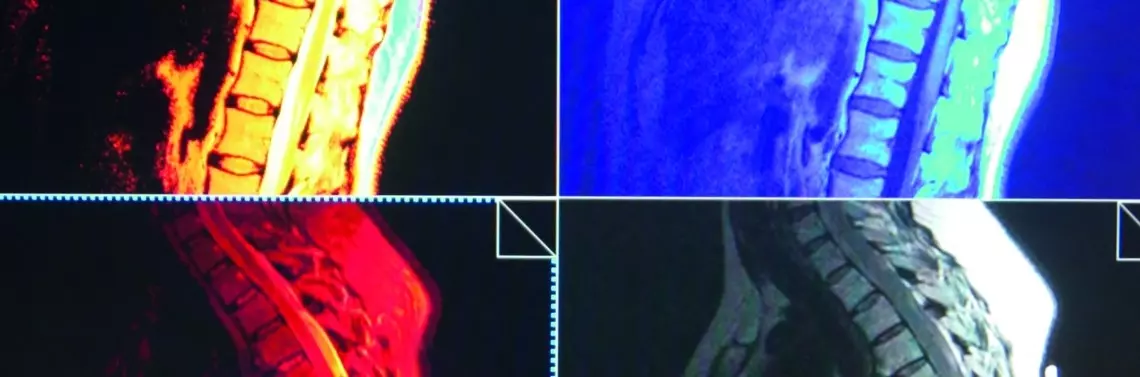

• Prezentacja metod obrazowania diagnostycznego kręgosłupa piersiowego

Z uwagi na ścisłą współzależność układu nerwowego somatycznego i autonomicznego w jego obrębie konieczne jest różnicowanie dolegliwości bólowych odczuwanych przez pacjenta w okolicy klatki piersiowej z bólami pochodzenia ściennego i trzewnego. W artykule omówiono anatomię i biomechanikę piersiowego odcinka kręgosłupa oraz obrazowe metody diagnostyczne umożliwiające ustalenie prawidłowego rozpoznania.